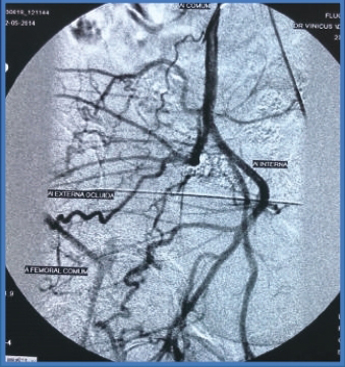

Clinical Case, EIA lesion

PREPOST